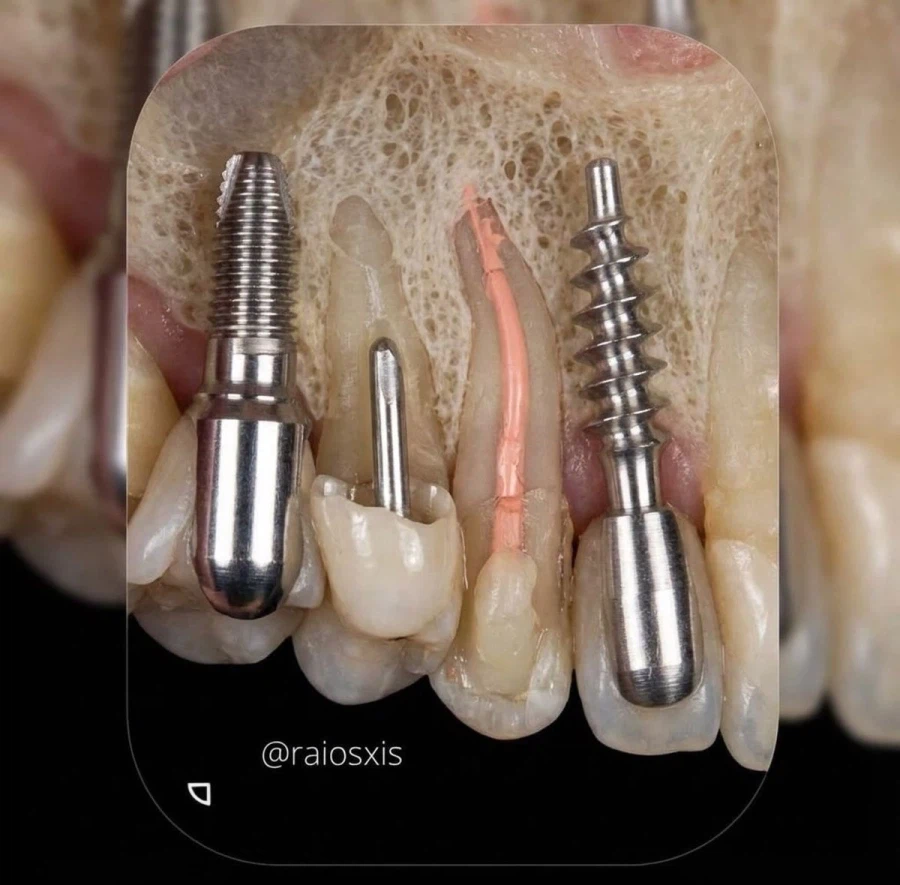

임플란트 잇몸 약하면 못하는 이유.jpg Anonymous | 2026.03.22 21:30 | 조회 7 https://qquing.net/bbs/board.php?bo_table=humor&wr_id=1863429 주소 복사 이전글 다음글 랜덤 만화 목록 본문 추천 0 비추천 0